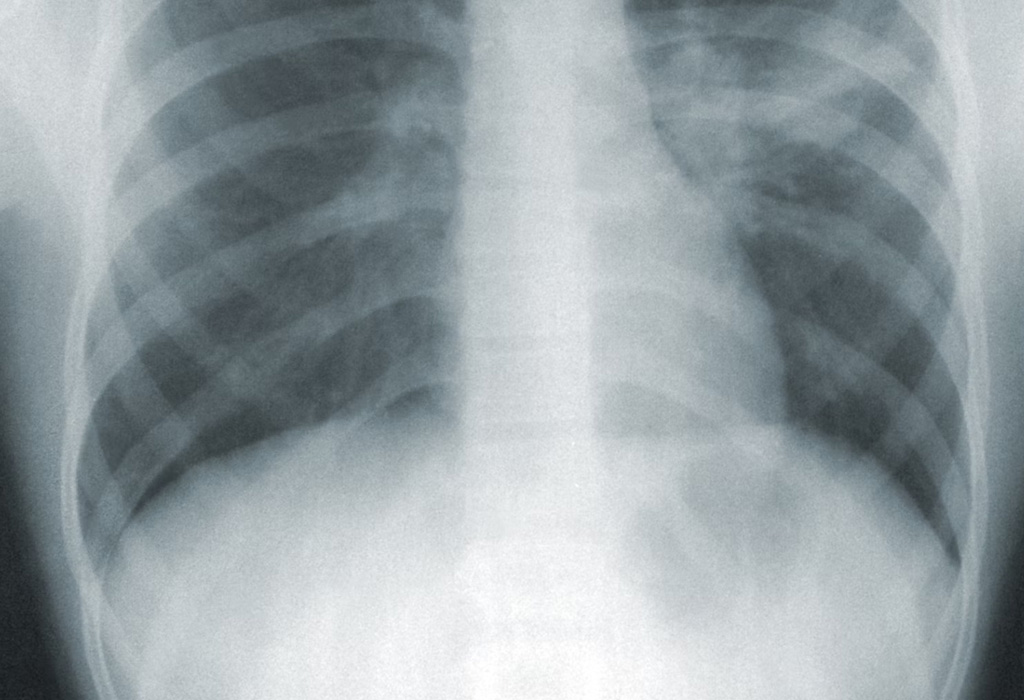

Radiographic scan of human

This concentration prepares students to become certified radiologic technologists, equipped to perform diagnostic X-ray procedures in clinical and hospital settings. Emphasis is placed on patient care, radiation protection, anatomy, and high-quality imaging techniques essential for accurate diagnosis and treatment.